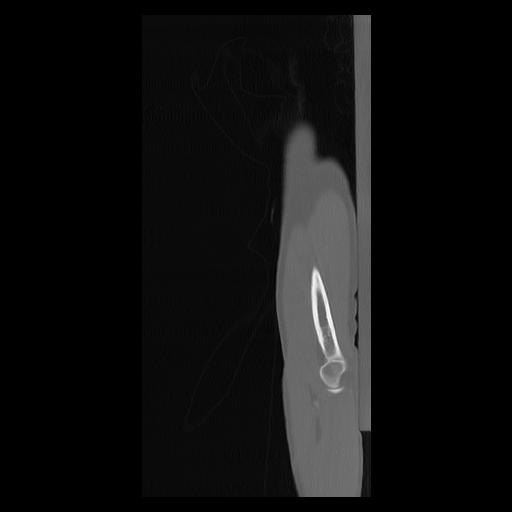

33 PULMON,CE,Sagittal,3.000,PULMON,Sagittal,